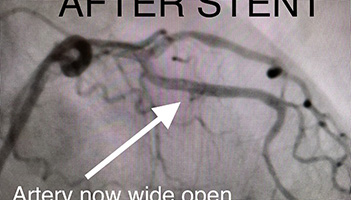

73 y/o female presents with accelerating symptoms of angina. Angiogram pictures show Left Anterior Descending artery (LAD) is severely blocked(stenosed). She receives an initial balloon dilatation and finally a drug eluting stent is implanted (see final result). She no longer has chest pain.